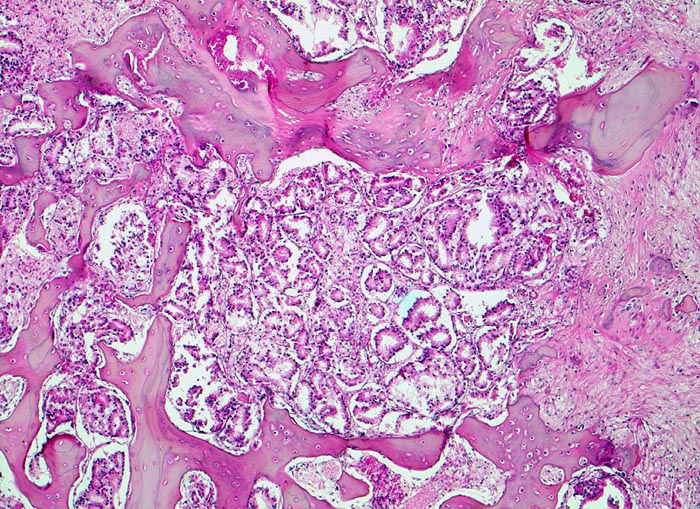

Prostatakarzinom: Knochenmetastase

Knochen, Wirbelsäule

Im Zentrum die kleinen dicht liegenden Karzinomdrüsen. Der Knochen wird stellenweise abgebaut. Fokal ist eine Faserknochenneubildung erkennbar.

Bei Autopsie finden sich zahlreiche, teils osteoplastische, teils osteolytische Metastasen im Bereich der Wirbelsäule. Die Karzinomdrüsen sind immunhistochemisch positiv für Prostata spezifisches Antigen.

Bekanntes metastasierendes Prostatakarzinom. St.n. bilateraler Orchiektomie. Diffuse Schmerzen im Bereich der Wirbelsäule. Der Patient verstirbt an einem Myokardinfarkt.